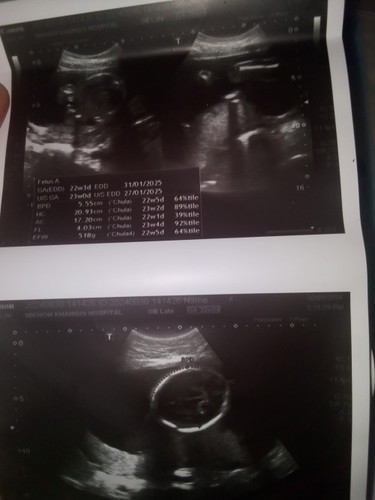

แม่ๆดูออกไหมค่ะดูไม่ออกเลยหมอบอกว่าผู้หญิง

5เดือนกว่า

น่าจะ ญ ตามหมอว่าค่ะแม่ หมอดูออก